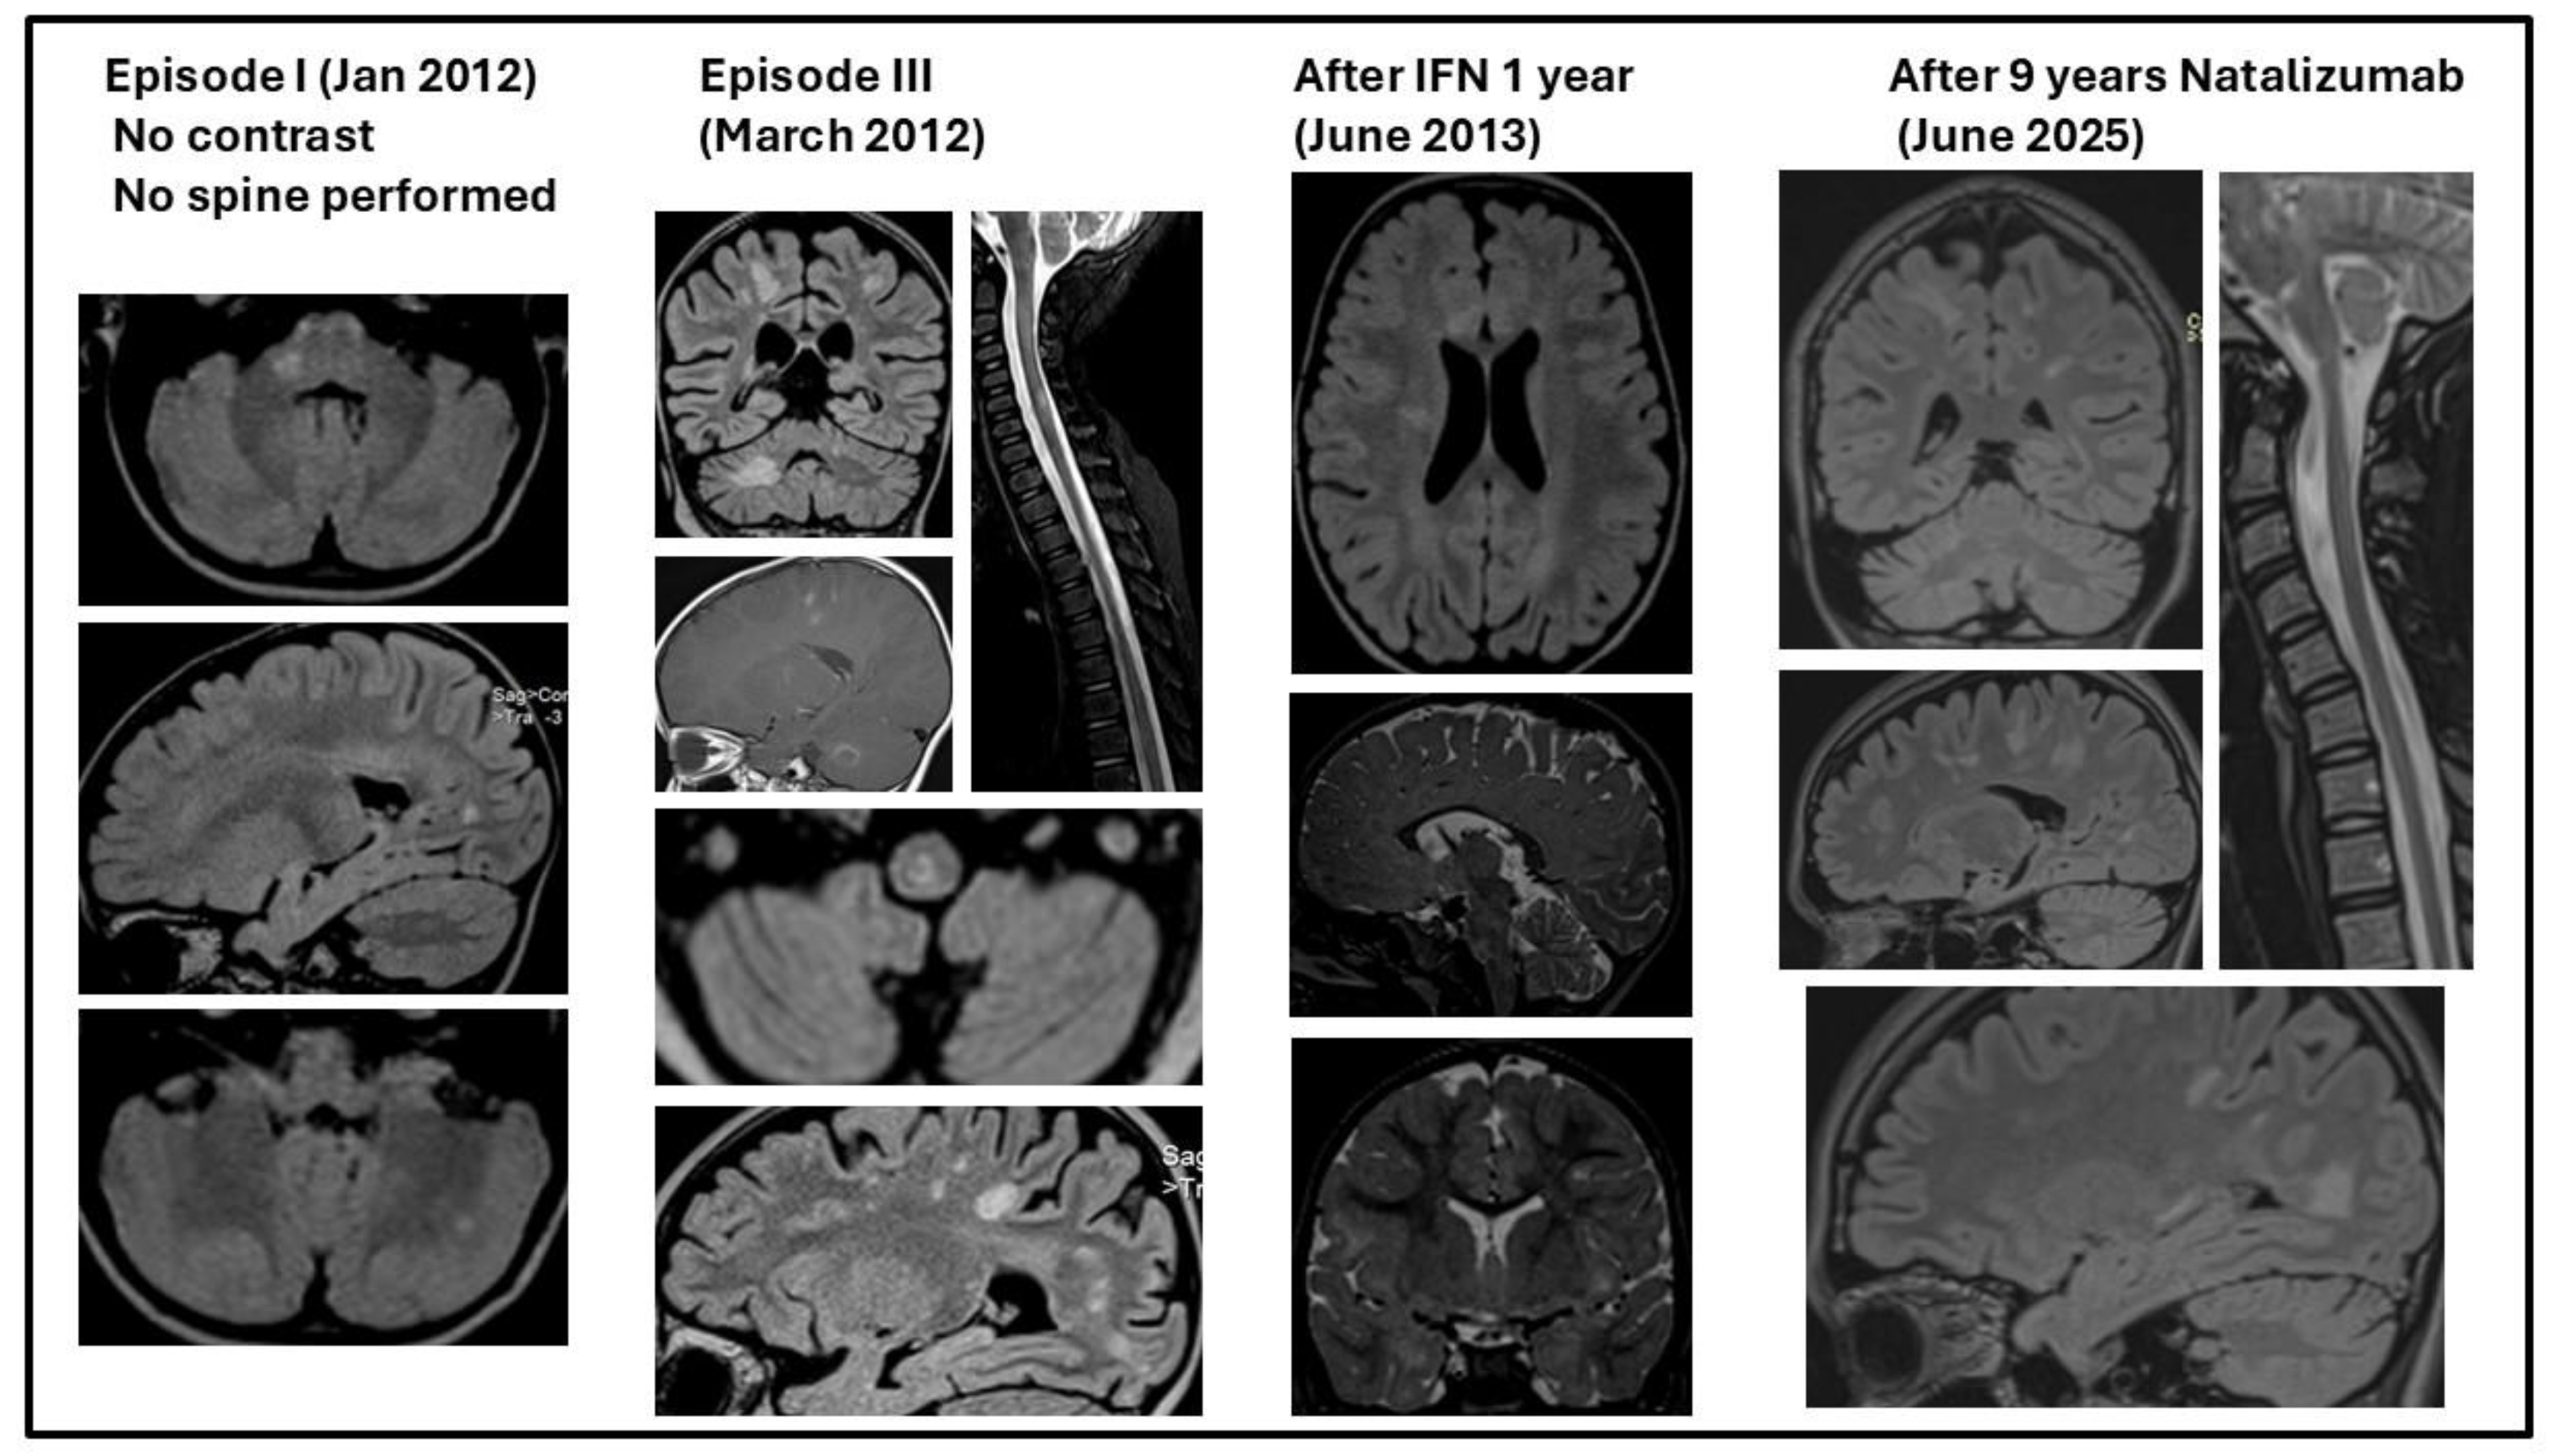

The diagnosis of RRMS was established at that time based on Mc Donalds criteria 2010 [29]: she had more than 2 attacks proving dissemination in time (DIT) and objective clinical and MRI evidence of dissemination in space (DIS). On MRI she had lesions in all 4 – periventricular, juxtacortical, infratentorial and spinal cord regions proving DIS; these lesions had different ages proving DIT (Figure 4).

The second episode started after 30 days (Table 5, Figure 3). No other investigations were carried out by the local physician. Treatment with Dexamethasone 8 mg/day – 3 days and Synachten 0.5 mg/day - 7 days was followed by complete remission within 5 weeks and another 35 days without neurological symptoms. MRI was performed at onset and after remission (Figure 4) of the third episode showing an increased number of MRI lesions.

Due to international collaboration with colleagues with experience in treating pediatric patients with Natalizumab, the patient was initiated at age 7 years on Natalizumab, 300 mg/dose, monthly administrations. Check-up for JCV (John Cunningham virus, Human polyomavirus 2) has been performed before and then monthly and MRI performed for PML (progressive multifocal leukoencephalopathy) at each relapse and yearly for follow-up; both JCV and MRI were done during IFN and Natalizumab therapies. No relapses were recorded after Natalizumab initiation during the next 9 years, until present; EDSS score decreased to 3.5 (persistent disability).

Figure 4. MRI at onset and in evolution.